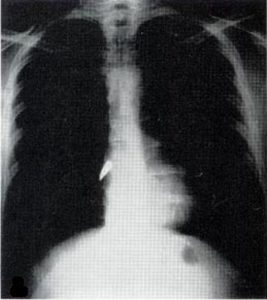

X-ray of a bullet in the heart. U.S. Army

X-rays, a type of electromagnetic radiation, had been discovered in 1895 by Curie’s fellow Nobel laureate, Wilhelm Roentgen. As I describe in my book “Strange Glow: The Story of Radiation,” almost immediately after their discovery, physicians began using X-rays to image patients’ bones and find foreign objects – like bullets.